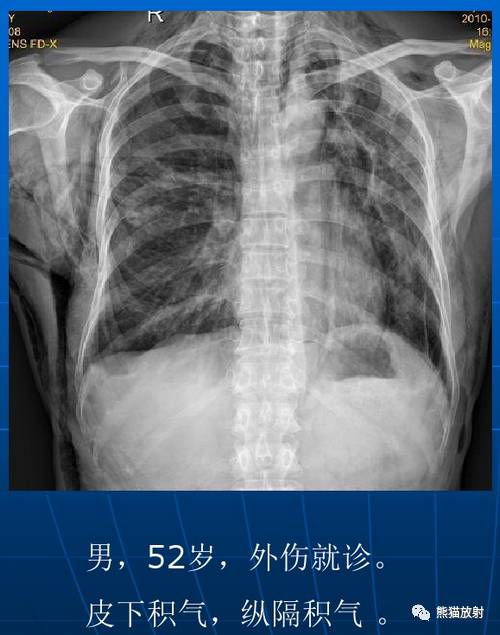

间质性肺气肿是由于支气管或肺泡破裂后,空气进入肺间质所引起。随后气体可沿着支气管和血管周围的间隙流入纵隔或心包产生纵隔积气或心包积气,并可到达皮下形成皮下积气。致病原因可为外伤性或自发性。

| 间质性肺气肿 |